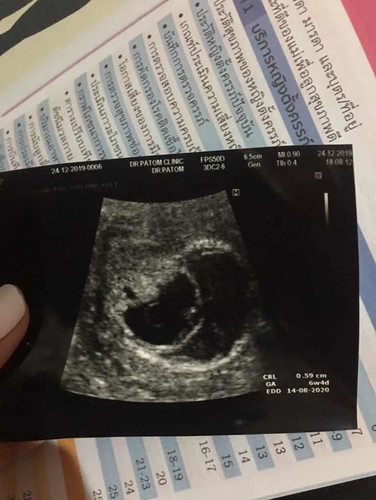

พึ่งไปซาวด์มาอายุครรภ์7week ได้ยินเสียงหัวใจน้องแล้วค่ะ คุณหมอบอกแต่มีคล้ายๆก้อนเลือดค่ะ อาจเกิดภาวะแท้งคุกคาม ใจคอไม่ดีเลยค่ะคุณหมอนัดตรวจอีก2อาทิตย์มาดูว่ามันจะแฟบลงหรือขยายใหญ่ขึ้น แม่ๆท่านไหนมีอาการเดียวกันไหมคะ กังวลจังค่ะ